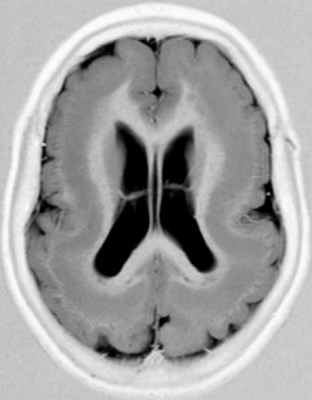

Если нейроны совсем не достигают коры, то возникает лиссэнцефалия. Если только часть нейронов не достигает её, то возникают субкортикальные гетеротопии, видимые при МРТ в виде узлов или полосы («двойная» кора). Клиническая симптоматика обычно негрубая – небольшое отставание развития, пирамидные знаки и, иногда, дизартрия.

МРТ. Т1-зависимая аксиальная томограмма. “Двойная кора”.

• Субкортикальная ламинарная гетеротопия и лиссэнцефалия в результате мутации DCX гена. Ленточные гетеротопии (Barkovich et al., 1994, Franzoni et al., 1995) или «двойная кора» (Livingston и Aicardi, 1990, Palmini et al., 1991) являются результатом нарушенной миграции, при которой поверхностная кора, внешне нормальная или с отклонениями в извилинах, отделена тонким слоем белого вещества от полосы серого вещества. Граница между серым веществом и подлежащим белым веществом ровная как при агирии-пахигирии. Пациенты с этой аномалией часто страдают судорогами, которые могут иметь очаговый или генерализованный характер, иногда в форме синдрома Ленокса-Гасто и аномальной ЭЭГ (Hashimoto et al., 1993, Parmeggiani et al., 1994).

Нарушения умственного развития значительно варьируют, некоторые пациенты развиваются нормально (Livingston и Aicardi, 1990, Ianetti et al., 1993). Barkovich et al. (1994) при детальном изучении 27 случаев обнаружили значительную корреляцию между интеллектуальным уровнем и толщиной гетеротопической полосы; внешне нормальная кора была связана с лучшим развитием, но, вероятно, этот признак может варьировать. На ЭЭГ было обнаружено, что полоса способна продуцировать пароксизмальную активность и повышенный кровоток, как было продемонстрировано с помощью ОФЭКТ, что указывает на активацию коры.

Субкортикальная групповая гетеротопия («двойная кора»):

(а) Аксиальный срез МРТ: широкие, непрерывные группы с таким же сигналом как от коры.

(б) Коронарный срез: в этом же случае имеется расширение желудочков преимущественно спереди.

(в, г) MPT, Т1-взвешенная последовательность — (в) аксиальный срез, (г) сагиттальный срез -тонкий слой белого вещества, лежащий между истинной корой и тонкой линейной гетеротопией серого вещества (стрелки).

Кроме того, была проведена магнитно-резонансная томография головного мозга (аппарат Hitachi Airis Mate 0,2 Тесла), согласно которой на аксиальных срезах определялись билатеральные лентовидные зоны, соответствующие серому веществу головного мозга, расположенные преимущественно субкортикально. Изгибы гетеротопированных слоев повторяли основную складчатость кортикальной поверхности. На коронарных срезах подтверждалось субкортикальное расположение гетеротопированных зон. В коре видимых диспластических изменений не отмечено. Таким образом, можно утверждать о наличии у пациентки МР-признаков билатеральной ламинарной гетеротопии серого вещества, что характерно для синдрома «двойной коры» (рис. 2).

Лентовидная гетеротопия, или синдром двойной коры, проявляется четко очерченным лентовидным слоем нейронов, отделенным от коры полосой белого вещества. Диагностировать данную патологию можно только по данным МРТ. При этом на изображениях выявляется ровная, четко очерченная полоса серого вещества, расположенная параллельно боковому желудочку и отделенная от коры и стенки желудочка слоем серого вещества. Кора мозга может быть неизмененной либо может быть изменена от умеренно выраженной пахигирии до полной агирии (рис. 3.21). В белом веществе на Т2-ВИ могут определяться очаги гиперинтенсивного сигнала. Лентовидную гетеротопию достаточно сложно дифференцировать с лиссэнцефалией: они, вероятно, представляют собой различные степени одного общего процесса нарушения миграции нейронов. В отличие от лиссэнцефалии, при лентовидной гетеротопии изменения коры выражены меньше.

Рис. 3.21. Лентовидная гетеротопия. МРТ.

а - IR ИП, аксиальная плоскость; б - Т2-ВИ, аксиальная плоскость.

Полоса гетеротопированного серого вещества отделена

слоем белого вещества от коры и желудочков мозга.